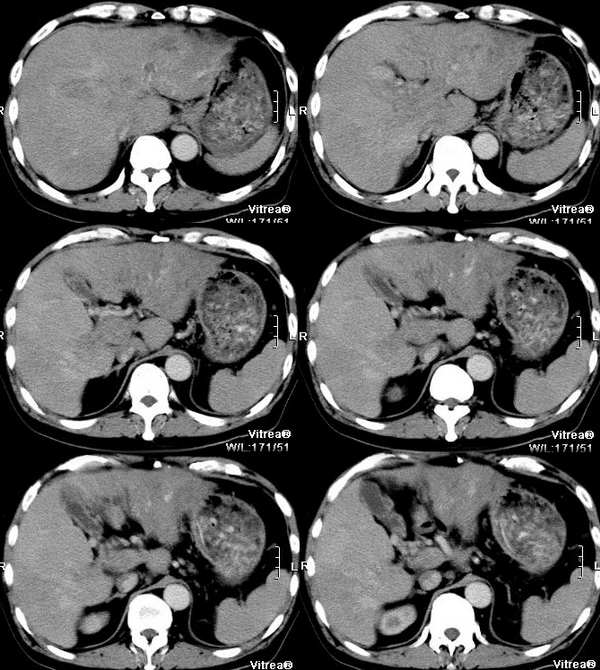

男性,58岁,肝硬化数年,近几个月出现黄疸,腹胀,食欲下降,尤其双下肢浮肿明显。超声提示肝脏多个结节。ct三期扫描图像如下:

这个病例最后结果是原发性肝癌合并门静脉、肝静脉、下腔静脉近心段以及右房癌栓形成,肝动-静脉瘘。afp:3200,dsa、彩超证实左心房及近心段下腔静脉有栓子(并有血供),肝中静脉内有癌栓,有异常血流,门静脉内充满癌栓

1 动脉期紧临下腔静脉的肝左叶显影明显------动静脉瘘造成;肝中静脉也显影但可见低密度充盈灶----癌栓形成;

2 门脉期示下腔静脉(肝门区至右心房段)与门静脉明显增粗,而且没有明显强化,可见充盈缺损,肝左右门脉分支无强化,--------静脉癌栓形成;门脉期肝脏显影不明显-----进一步证实了门脉癌栓;右心房内造影剂没有完全填充-----说明心房内有癌栓形成;

3 动脉期肝左外叶多支动脉血管显影-----说明病灶动脉供血明显,而且多发,之所以病灶强化不明显原因可能与动脉期扫描时间较早有关(脾脏没有显影),而且门脉期肾脏显影还不够,进一步证实了这一点;因为肝硬化的病人肝动脉比较细,动脉期的延迟时间应该往后放放(一般螺旋ct延迟时间采用30秒左右)同时还跟动静脉瘘有关;延迟期(称门脉期不为过)病灶显影较明显进一步证实了快进快出的强化特点;一些网友对肝细胞肝癌和胆管细胞癌的诊断还是有些疑问,为什么胆管扩张还有黄疸呢??这应该是胆管细胞癌的专利呀!!其实肝细胞肝癌也可以合并胆管扩张,扩张的原因主要是胆管内肿瘤的侵润形成胆管内瘤栓所致;再结合门脉与腔静脉瘤栓,

以及\"快进快出\"的强化特点,应该能够诊断肝细胞性癌;

4 肝内胆管轻度扩张,以肝左外叶明显,进一步证实了胆管内瘤栓的可能;

5既然门脉与肝静脉内都有癌栓,那么肝细胞癌肝内转移的可能性很大,因此肝内多发病灶内肯定有转移灶的可能,这进一步与b超多发占位吻合;

6结合病史肝硬化,胆管细胞癌可以肯定的排除了!!